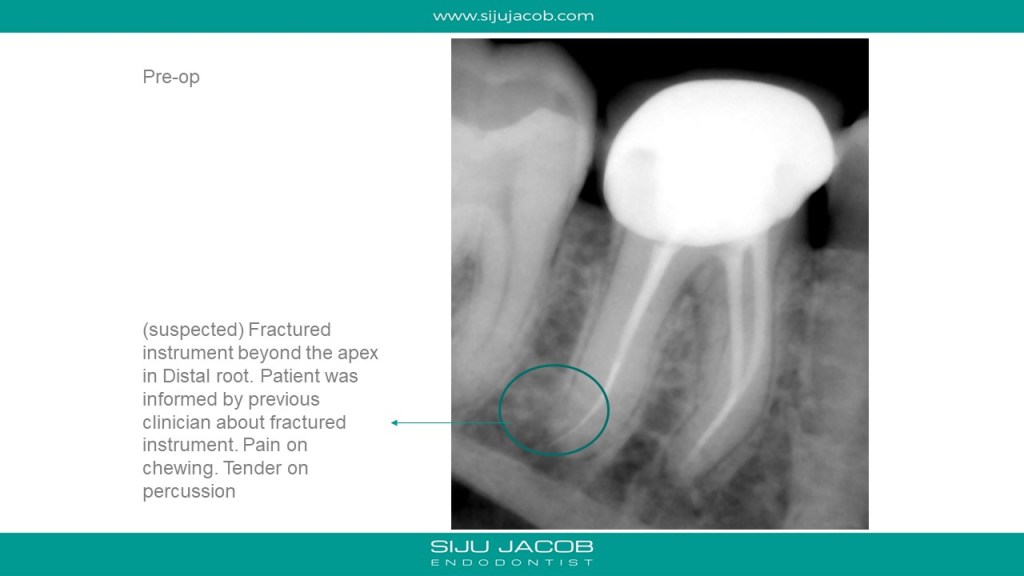

This patient had Endo and crown done a few months ago. While doing the endo, the previous clinician had informed him that she had fractured an instrument and that she couldn’t remove it because it had gone slightly beyond the apex. The mesial canals seemed well-filled. So, I Re-treated only the Distal. Fortunately, the distal canal was ovoid with plenty of access and visualization all the way to the apex. I was able to retrieve the instrument by braiding two H-files on either side of the fragment.